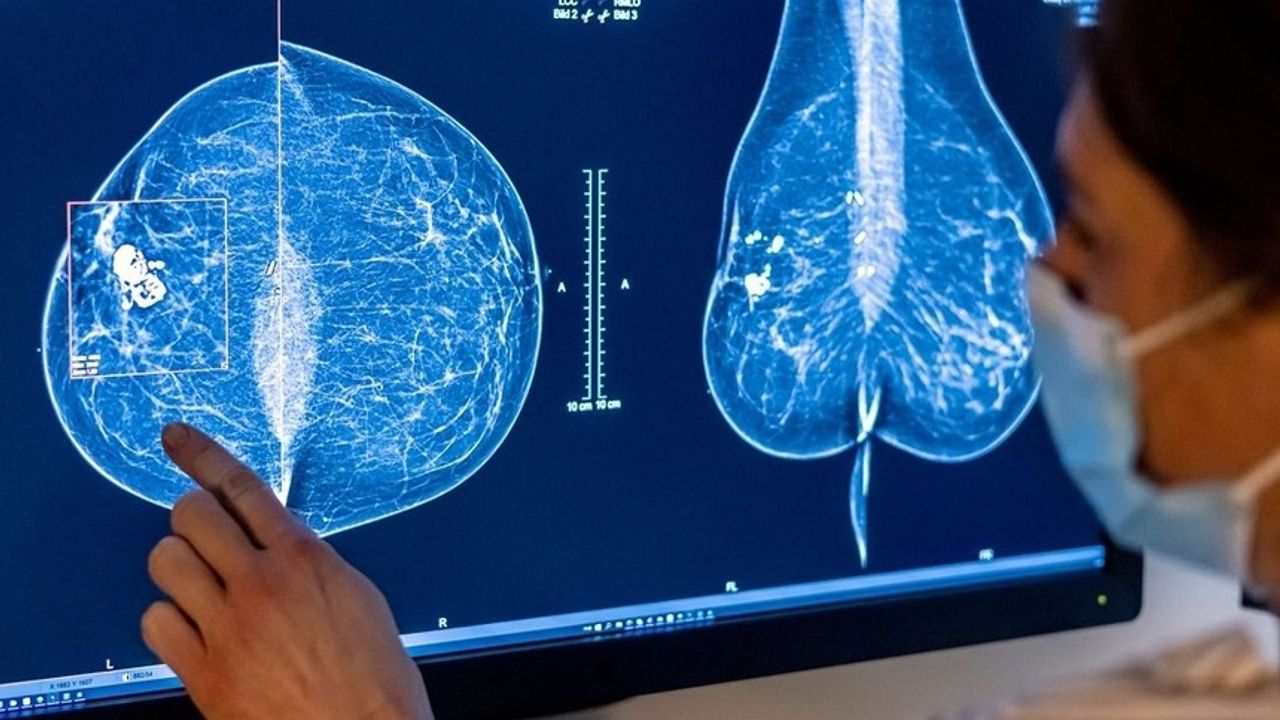

Genç kadınlarda meme kanserinde artış

Raporda dikkat çeken bir diğer nokta ise genç kadınlarda meme kanseri vakalarındaki artış oldu. 30–49 yaş arası kadınlarda meme kanseri görülme sıklığı, 1999 yılında her 100 bin kişide 85,9 iken, 2023’te 107,8’e yükseldi. RKI, bu artışta 2009 yılında ülke genelinde başlatılan mamografi tarama programlarının da etkili olabileceğine işaret ediyor.